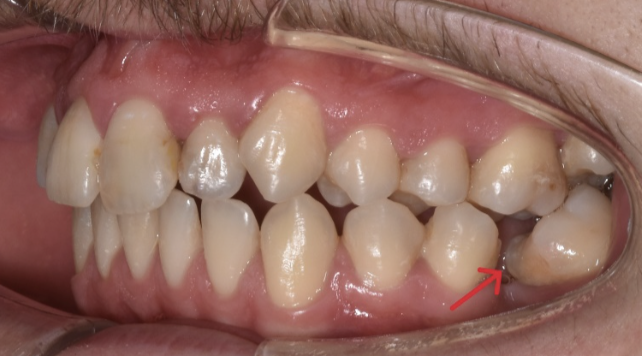

Dupa o extractie dentara, dintii vecini se inclina in cautarea de puncte de contact.

Daca nu se inlocuieste dintele in scurt timp, spatiul se reduce si nu va mai fi sufficient pentru aplicarea unui impland dentar.

Cu ajutorul ortodontiei, putem indrepta dintii migrati si restabili dimensiunea zonei pentru o refacere estetica si functionala

Aici avem un caz in care inghesuirea dentare grava s-a rezolvat prin tratament orthodontic cu extractii dentare.

Se poate observa ca nu exista spatiu pentru eruptia caninilor.